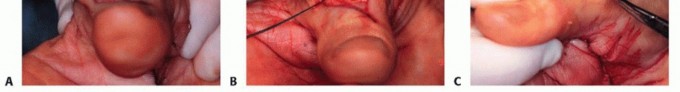

The retinaculum is elevated radially and ulnarly to unroof compartments one through six. A radical tenosynovectomy is performed. The hypertrophic, invasive pannus is meticulously dissected away from the surviving extensor tendons using sharp dissection and tenotomy scissors. Care must be taken to preserve the vincula and the intrinsic blood supply to the remaining intact tendons.

Once the tendons are cleared, the extent of the ruptures is definitively cataloged. The ruptured ends are typically frayed, attenuated, and encased in fibrotic scar tissue.

The diseased proximal and distal stumps are sharply debrided back to healthy, organized collagen.